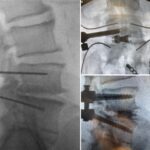

T/PLIF Solutions

T/PLIF

Heights 7mm* expanding to 17mm*

Width 12mm expanding to 21mm

0°, 8°, 12° and 15° Lordosis*

TLIF